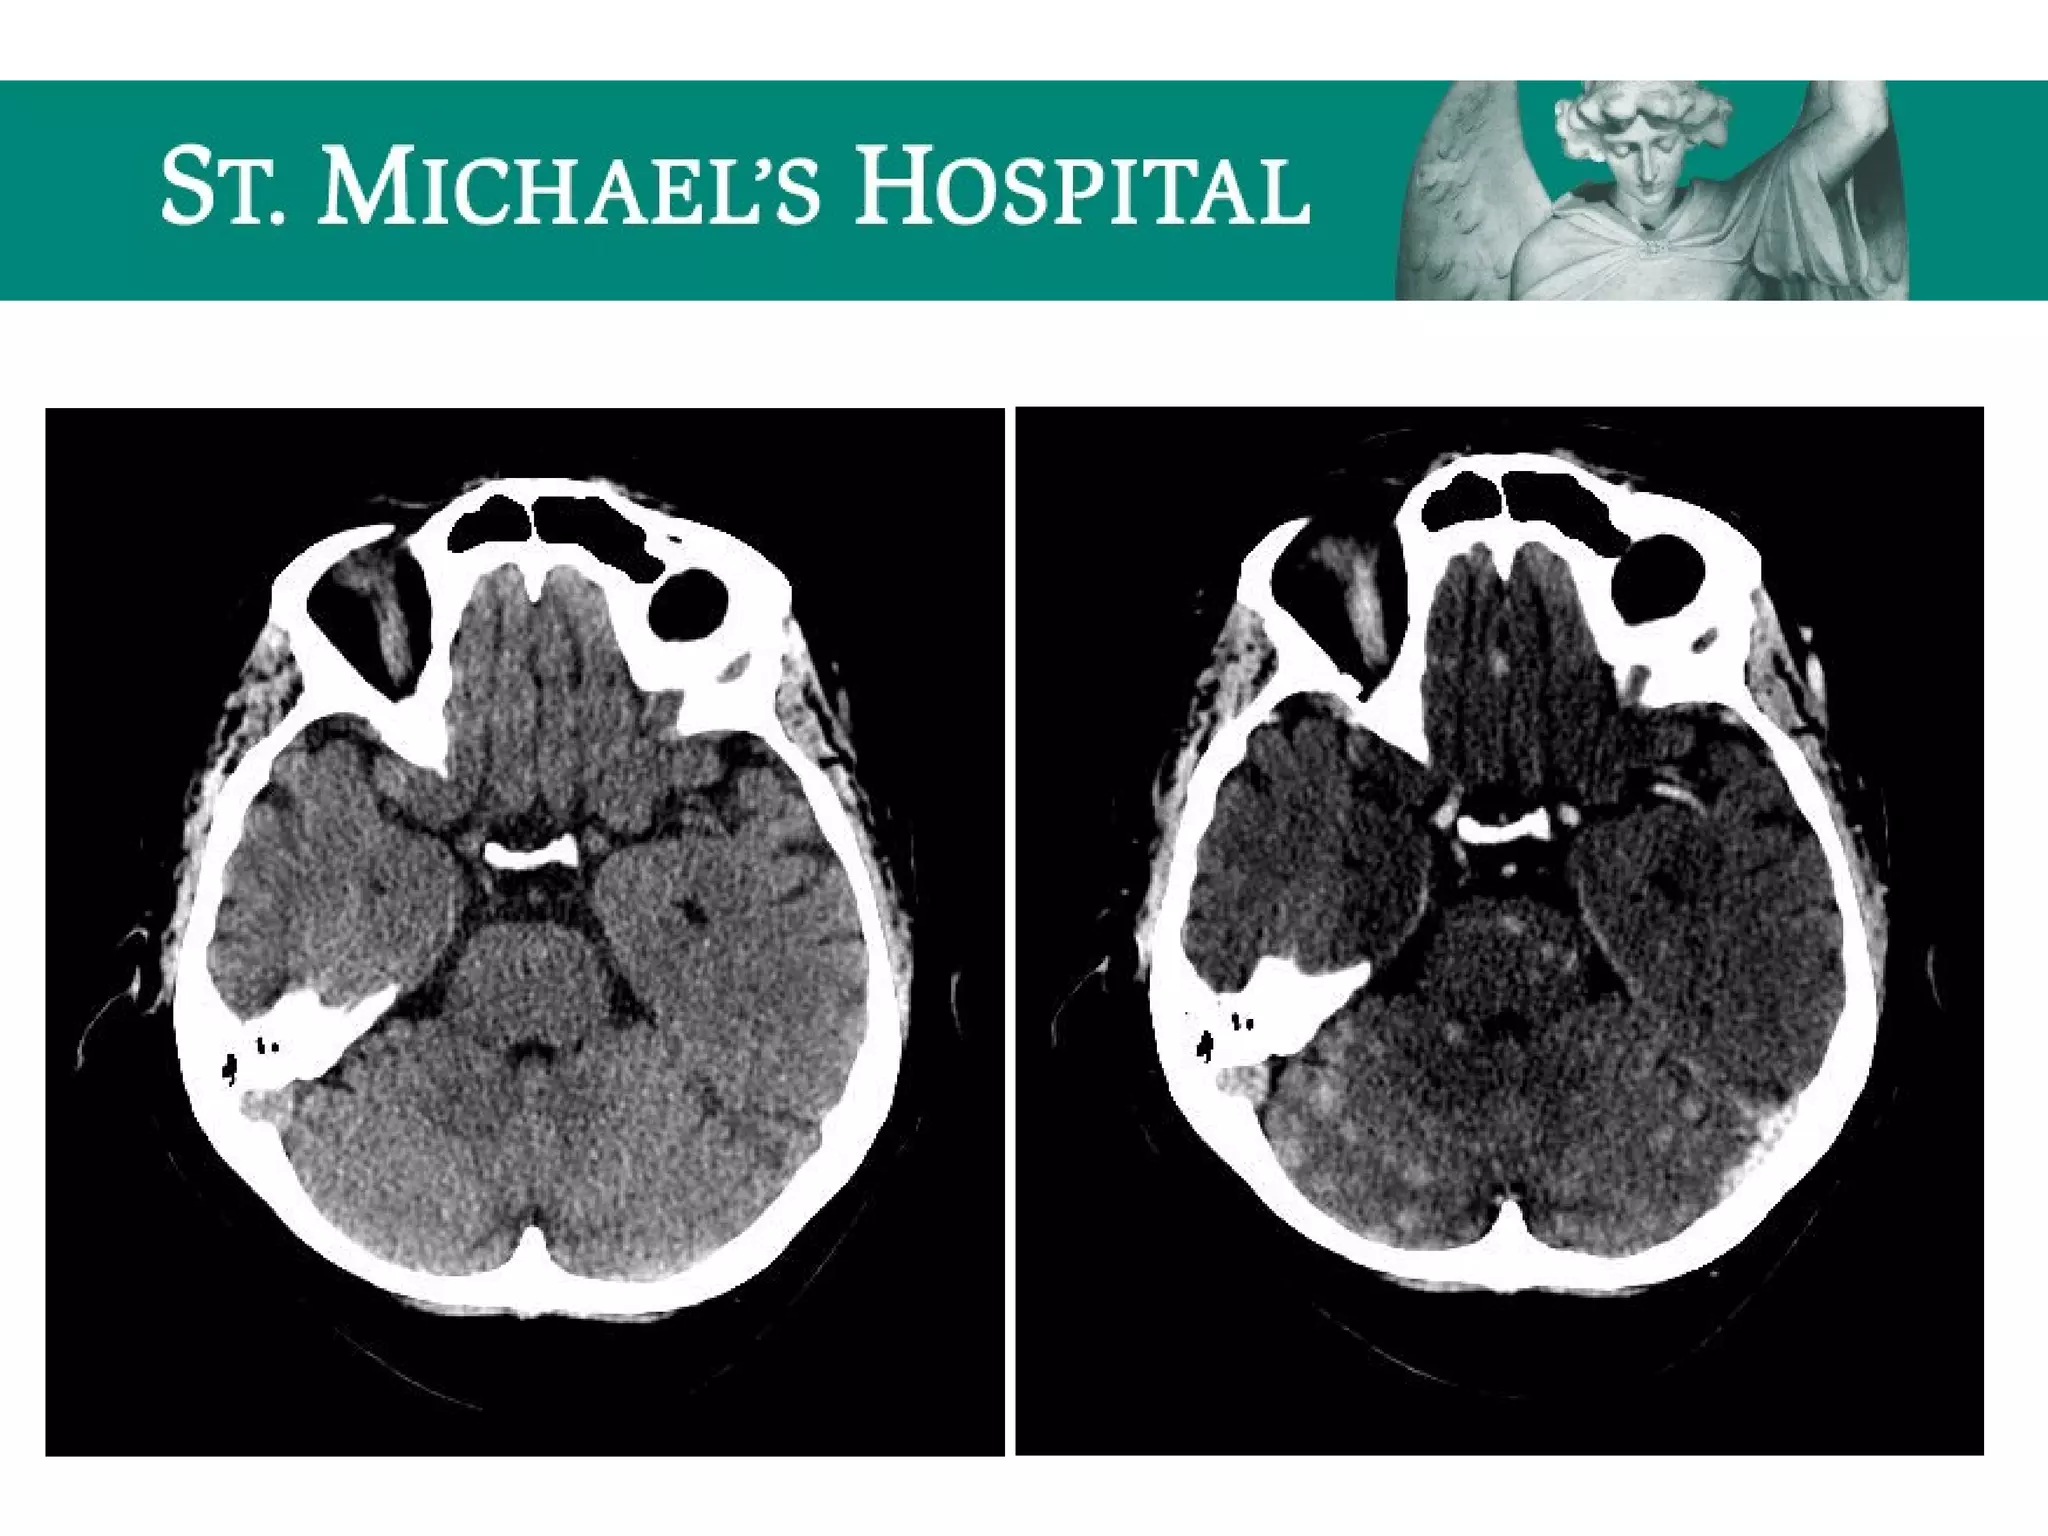

SDH – CT Features

 Acute SDH

 high density fluid collection layering along the cerebral convexity

 crescentic (concave inner margin/convex outer margin)

 associated mass effect (sulcal effacement, ventricular compression, midline shift)

 Subacute SDH (1-2 weeks)

– “isodense” to grey matter

 Chronic SDH (> 2 weeks)

– “hypodense” to gray matter

– “acute-on-chronic”  hyperdense acute hemorrhage intermixed or layering dependently

within the chronic collection.